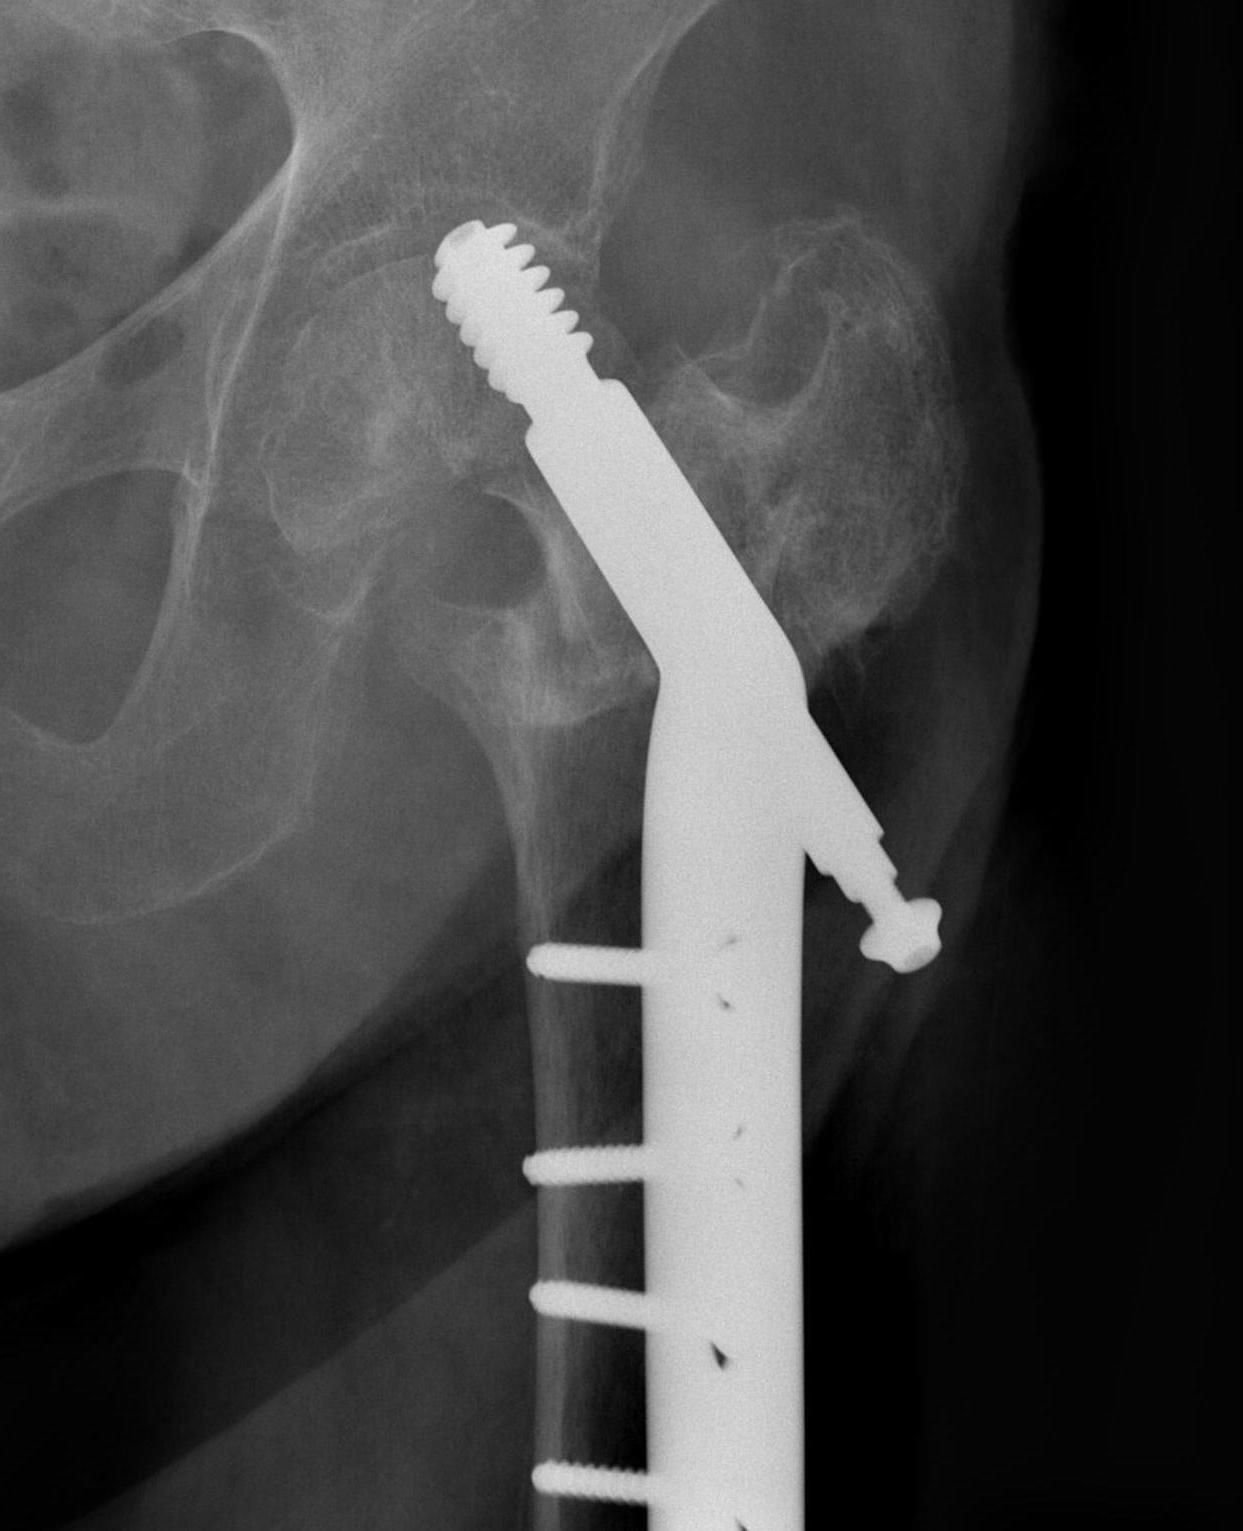

Cephalomedullary nail / Proximal femoral nail

Mechanical advantages

- load sharing rather than load bearing

- decreases lever arm

- supports medial cortex

Surgical advantages

- smaller incision / minimally invasive

- reduced blood loss

- shorter surgical times

Indications

- reverse oblique

- unstable fracture / loss of lateral buttress / loss posteromedial support

- subtrochanteric extension